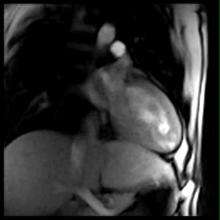

Real-time magnetic resonance imaging (MRI) refers to the continuous monitoring ("filming") of moving objects in real time. Because MRI is based on time-consuming scanning of k-space, real-time MRI was possible only with low image quality or low temporal resolution. Using an iterative reconstruction algorithm these limitations have recently been removed: a new method for real-time MRI achieves a temporal resolution of 20 to 30 milliseconds for images with an in-plane resolution of 1.5 to 2.0 mm.[2] Real-time MRI promises to add important information about diseases of the joints and the heart. In many cases MRI examinations may become easier and more comfortable for patients.

Although applications of real-time MRI cover a broad spectrum ranging from non-medical studies of turbulent flow [9] to the noninvasive monitoring of interventional (surgical) procedures, the most important application making use of the new capabilities is cardiovascular imaging.[1] With the new method it is possible to obtain movies of the beating heart in real time with up to 50 frames per second during free breathing and without the need for a synchronization to the electrocardiogram.[10]